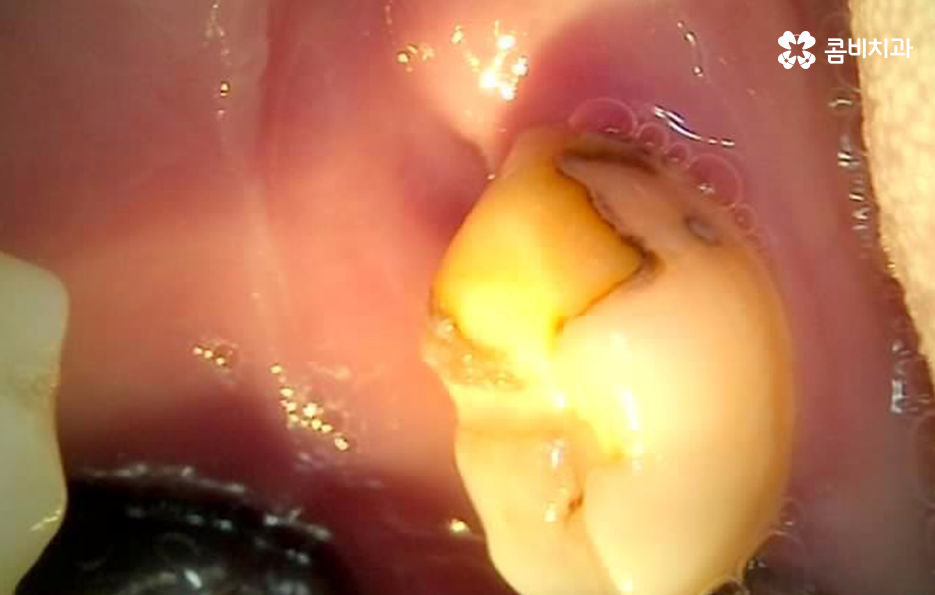

치아가 안아파도 명동치과 매년 주기적으로 검진하고 스케일링을 하시라고 권장하는 이유도 이러한 2차충치에 대한 우려 혹은 보철물의 교체 주기 및 수명을 체크하는 이유도 있겠고 사랑니 상태나 치아의 인접면에 발생하는 충치와 같이 평소 눈으로는 살펴보기 어려운 치아 문제를 치과에서 정확하게 파악하려는 목적이 크다고 할 수 있어요

이처럼 2차충치가 치아 내부로 진행된 경우에는 치아 구조의 특성상 치아의 겉면에 비해 내부가 좀더 약하기 때문에 충치는 비교적 쉽게 내부로 깊어질 우려가 있으며 신경조직에 손상이 발생한 경우에는 신경치료를 해야 하기 때문에 자연치아의 손상이 그만큼 커질 수 있어요

이러한 문제는 치아 내부에서 발생하기 때문에 눈으로 살펴볼 때는 상태 확인이 어렵고 명동치과 주기적으로 검진을 하지 않는다면 통증을 통해 뒤늦게 문제를 인지하기 때문에 치료 시점도 초기치료는 놓친 경우가 대부분이라 할 거예요

오늘 소개드린 2차충치 만큼이나 예방이 중요한 치아 문제는 치아의 인접면 즉 치아 사이에 발생한 충치라고 할 수 있는데요. 사실 2차충치나 인접면 충치 모두 기본적으로 평소 칫솔질도 잘하고 특히 치실 사용을 잘하는 것이 구강 내 세균 관리에서 평소 실천할 수 있는 구강관리 방법이며 명동치과 매년 최소 1회는 검진과 스케일링을 꼭 필수적으로 실천하는 것도 강조드리고 있어요